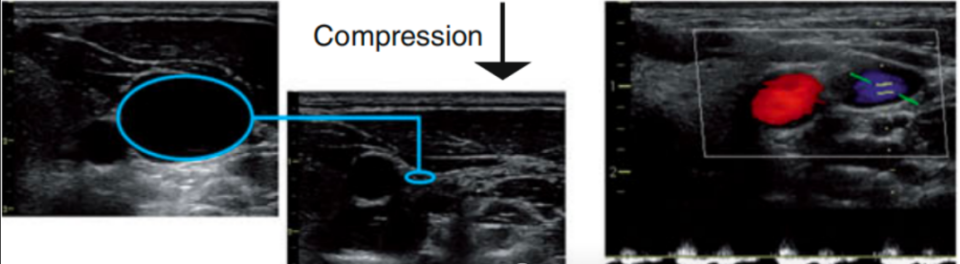

①加压法

由于静脉血管缺乏富含弹性纤维的中膜,管壁较薄,相对于伴行的动脉更容易被压闭,因此可以通过探头加压的方式来观察,首先被压闭的是静脉。